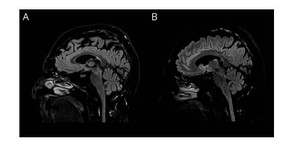

A 52-year-old man was admitted because of subacute-onset vertigo, dysarthria, vomiting, and weight loss. He was under atezolizumab (anti–PD-L1) monotherapy (23 cycles) for metastatic small-cell lung cancer, with excellent response.